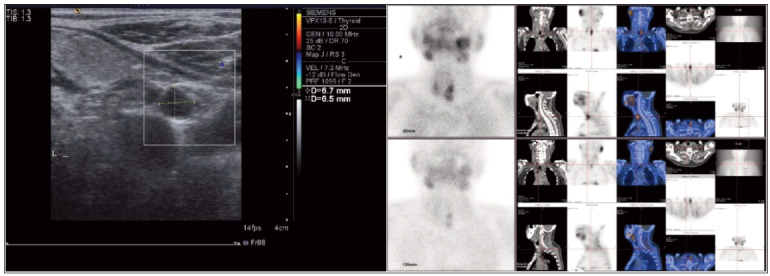

Background: This study aimed to evaluate the effect of combining paricalcitol with cinacalcet on the levels of intact parathyroid hormone (iPTH) and alkaline phosphatase (ALP) in patients with secondary hyperparathyroidism undergoing maintenance hemodialysis (MHD).

Methods: A retrospective analysis was conducted on the clinical records of 129 patients diagnosed with chronic kidney disease (CKD) and secondary hyperparathyroidism who received MHD between June and December 2022. The patients were categorised into three groups based on their treatment regimen: Group A (paricalcitol alone, n=43), Group B (cinacalcet alone, n=43), and Group C (combined paricalcitol and cinacalcet, n=43). Hemoglobin (Hb), serum albumin (Alb), calcium (Ca), phosphorus (P), iPTH, ALP, serum creatinine (Scr), and blood urea nitrogen (BUN) levels were measured at admission, 1 day, 3 months, and 6 months to compare the outcomes across the three groups.

Results: No significant differences among the groups were observed in Hb and Alb levels at 1 day post-admission (P>0.05). However, after 3 and 6 months of treatment, Hb and Alb levels increased in all groups, with Group C showing the greatest improvement (P<0.05). iPTH, Ca, and P levels were similar across all groups on day 1 (P>0.05), but by 3 and 6 months, all groups showed reductions, with Group C having the lowest levels (P<0.05). Similarly, ALP, Scr, and BUN levels decreased in all groups over time, with Group C again demonstrating the greatest reduction (P<0.05).

Conclusions: The combination of paricalcitol and cinacalcet was effective in reducing iPTH, calcium, phosphorus, and ALP and improving Hb and Alb levels in patients with secondary hyperparathyroidism on maintenance hemodialysis. This treatment approach offers significant benefits in managing SHPT.